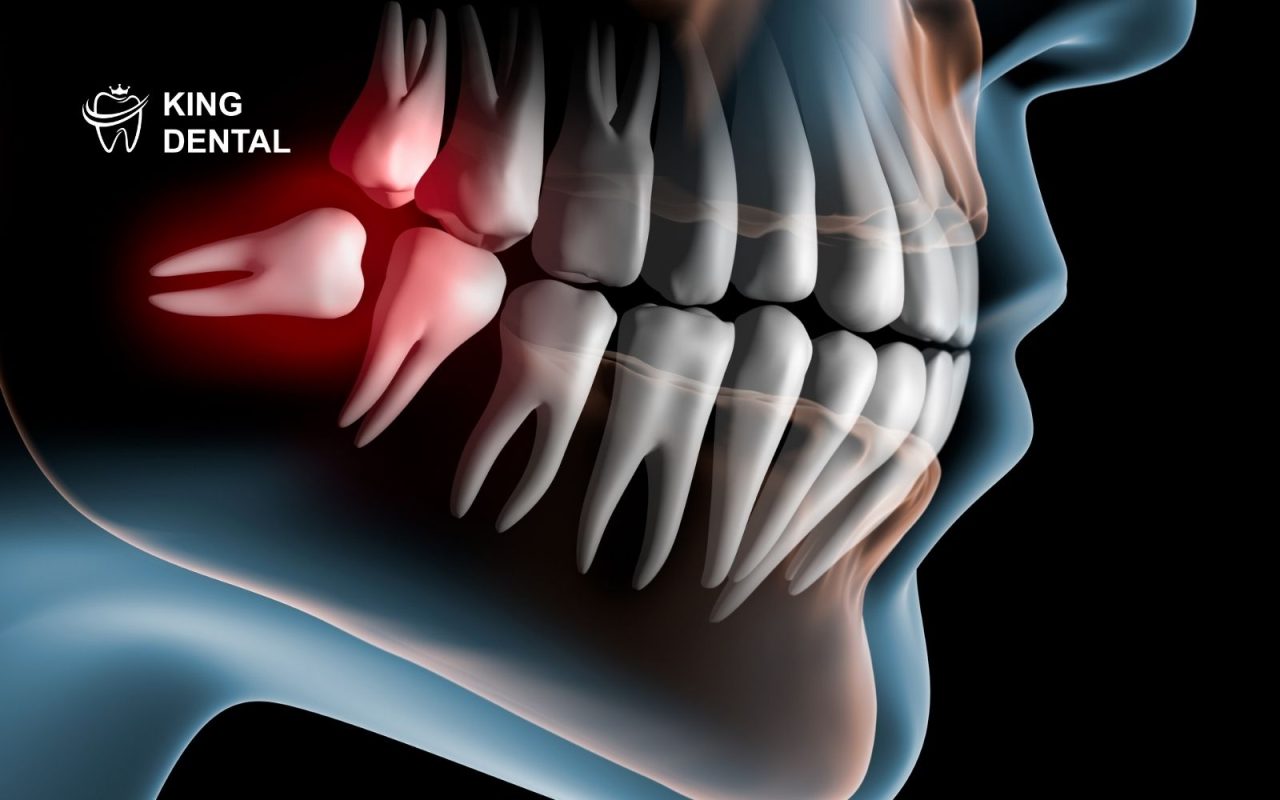

2. Tại sao mọc răng khôn lại gây đau và khó chịu?

Nhiều người thắc mắc tại sao mọc răng khôn lại gây ảnh hưởng lớn đến sức khỏe răng miệng. Lý do liên quan đến vị trí răng và cấu trúc xương hàm.

- Xương hàm không còn đủ chỗ

Răng khôn mọc muộn nên ít không gian. Điều này khiến răng đâm vào răng bên cạnh.

- Răng khôn mọc sai hướng

Răng có thể mọc xiên hoặc mọc ngang. Điều này gây chèn ép và viêm kéo dài.